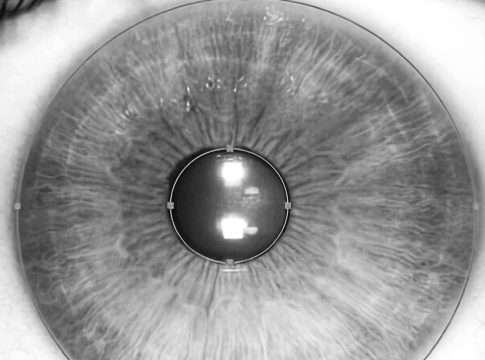

Un ejemplo de ello es el nuevo láser para cambiar color de ojos creado por los expertos oftalmólogos de Clínica Eyecos, llamado NewEyes 7G Ultimate Custom Laser, un dispositivo equipado con la más avanzada tecnología, que lo convierte en un óptimo láser para cambiar el color de los ojos de manera segura y predecible.

Lo último en tecnología láser para cambiar el color de ojos: NewEyes 7G Ultimate Custom Laser

La tecnología de NewEyes 7G Ultimate Custom Laser se ha consolidado a día de hoy como una de las técnicas más avanzadas para cambiar el color del iris de una manera eficaz, segura y predecible. Sus resultados son extraordinariamente naturales, y lo mejor es que prácticamente no genera ningún contratiempo para el paciente, careciendo de las complicaciones clínicas generalmente asociadas a las intervenciones oculares. Además, NewEyes 7G Ultimate Custom Laser es un óptimo láser para cambiar el color de ojos, porque permite que el procedimiento se haga de manera ambulatoria y no quirúrgica, de forma más rápida, cómoda y segura para el paciente. Por otro lado, también hay que destacar que la tecnología NewEyes 7G Ultimate Custom Laser de Clínica Eyecos cuenta con una tasa de eficacia muy alta, logrando eliminar de manera satisfactoria el pigmento melánico de la cara anterior del iris en casi el 100 % de los casos, consiguiendo resultados extraordinarios.

Cuando se habla del cambio de color de los ojos mediante láser, muchas personas tienden a cuestionarse si el proceso realmente no conlleva riesgos. En el caso del NewEyes 7G Ultimate Custom Laser, su uso ha probado ser altamente seguro. De hecho, tras miles de intervenciones realizadas por la clínica, hasta el momento, no se han observado cambios refractivos, elevación de la presión intraocular o disminución de la agudeza visual una vez completado el tratamiento. Además, hay que destacar que para Clínica Eyecos la seguridad del paciente es una prioridad, por lo cual siempre se realiza una previa y rigurosa evaluación del paciente, para así determinar si puede o no ser un candidato para el tratamiento. Hacer esto es precisamente uno de los pasos más importantes, que ayuda a mantener una tasa de efectividad tan alta.